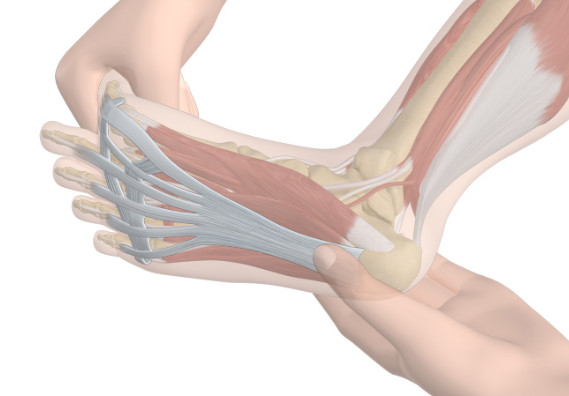

족저 근막염 치료법 ⑧ 족욕과 마사지

족욕과 마사지도 좋은 치료법입니다. 냉온욕이 가장 좋은데, 따뜻한 물 10분, 찬 물 10분, 이렇게 40분간 족욕을 해주시면 됩니다. 그리고 마사지 오일을 구매하여 종아리를 전체적으로 마사지해 주는 것도 도움이 됩니다. 통증이 있는 곳은 마사지할 수 없으므로 그 주위의 혈액순환을 도와주는 마사지를 해주면 됩니다. 종아리 마사지는 꼭 해주시길 바랍니다.